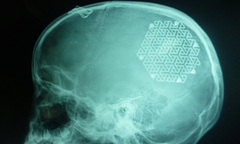

Với phương pháp tạo hình hộp sọ bằng tấm kim loại (titanium), các bác sĩ Bệnh viện Hữu nghị Việt Nam - Cu Ba Đồng Hới đã phẫu thuật tái tạo thành công hộp sọ cho bé gái